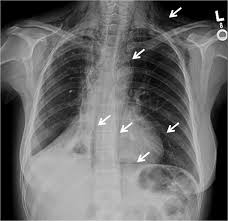

Hemoptysis Evaluation And Management American Family Physician from www.aafp.org Malignant tumors trigger inflammation in surrounding normal lung tissue, and they may obstruct your airways and interfere with normal airflow. This can lead to misdiagnosis as conditions such as irritable bowel syndrome (ibs). In this article they describe a variety of pulmonary conditions that can present with imaging features mimicking those of primary lung cancers. Pneumonia is a lung infection that leads to breathing difficulties and fluid in the lungs. When sarcoidosis affects the lungs, symptoms can mimic idiopathic pulmonary fibrosis including shortness of breath and a dry cough. Pneumonia can be mild and only require a week of treatment before you can. Pneumonia in people with lung cancer. Although slipping from emphysema to copd is usually not a drastic decline in health, early detection of lung cancer is critical for increasing your treatment options and improving your prognosis.

Risk Factors Of Lung Cancer In Chronic Obstructive Pulmonary Disease Download Scientific Diagram from www.researchgate.net Part of the dilemma for doctors is the significant overlap between copd symptoms and lung cancer symptoms. A fungal infection called valley fever, which can cause mild to severe lung problems (including holes in the lungs), is often misdiagnosed because the symptoms can resemble those of the flu or. Copd is a major risk factor for lung cancer. This, in turn, may cause collapse of the air sacs surrounding the tumor. We'll also look at some methods and medical tests commonly used. But, time is of the essence. But recent evidence suggests that copd itself is an independent risk factor for developing lung cancer, separate from any smoking history. By the time the doctor recognizes that treatment has not worked and more testing or a specialist is needed, valuable time is wasted.

Early Detection Of Copd Is Important For Lung Cancer Surveillance European Respiratory Society from erj.ersjournals.com Copd has been linked to smoking, so simply not smoking, or quitting, will greatly reduce your risks of suffering from this condition. But, time is of the essence. When detected in its earliest stages, lung cancer can often be successfully treated and sometimes even cured. In this article they describe a variety of pulmonary conditions that can present with imaging features mimicking those of primary lung cancers. Pulmonary emboli are blood clots that have formed in other regions of the body and have then traveled to the lungs. However, the symptoms of lung cancer differ vastly from bronchitis which is one of the commonest affections of chronic smokers. Pancreatic cancer may also be misdiagnosed as gallstones or pancreatitis, or the inflammation of the pancreas. Can lung cancer be mistaken for copd?